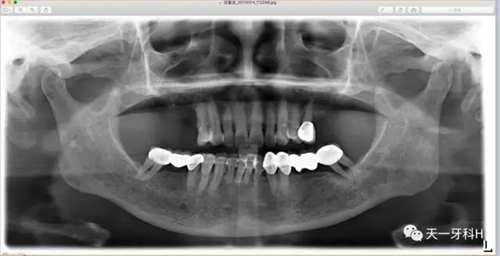

該患者2004年3月16日來本診所就醫(yī),這張曲面斷層片就是當時拍的,患者之前在外院后牙區(qū)全部做了烤瓷連橋,從這張曲面斷層片上看:右上七牙槽骨已經(jīng)破壞到了根尖,右上五也出現(xiàn)了牙周膜間隙增寬,左上后牙的烤瓷橋的基牙也開始出現(xiàn)問題了,我常常講:牙周病患者盡量不要做烤瓷牙,很多患者不理解,我用事實說話:這個牙周病患者就是一個烤瓷牙的受害者,四個后牙區(qū)全部做了烤瓷橋!17已經(jīng)牙槽骨破壞到達了根尖區(qū),15、25、28已經(jīng)開始了牙槽骨破壞,我當時勸她拆除烤瓷橋,她不聽我的話,我只好拍片記錄下來她的現(xiàn)狀,下面就是她當時的牙片: